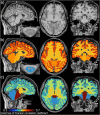

Clinical research emphasizes the implementation of rigorous and reproducible study designs that rely on between-group matching or controlling for sources of biological variation such as subject's sex and age. However, corrections for body size (i.e. height and weight) are mostly lacking in clinical neuroimaging designs. This study investigates the importance of body size parameters in their relationship with spinal cord (SC) and brain magnetic resonance imaging (MRI) metrics. Data were derived from a cosmopolitan population of 267 healthy human adults (age 30.1±6.6 years old, 125 females). We show that body height correlated strongly or moderately with brain gray matter (GM) volume, cortical GM volume, total cerebellar volume, brainstem volume, and cross-sectional area (CSA) of cervical SC white matter (CSA-WM; 0.44≤r≤0.62). In comparison, age correlated weakly with cortical GM volume, precentral GM volume, and cortical thickness (-0.21≥r≥-0.27). Body weight correlated weakly with magnetization transfer ratio in the SC WM, dorsal columns, and lateral corticospinal tracts (-0.20≥r≥-0.23). Body weight further correlated weakly with the mean diffusivity derived from diffusion tensor imaging (DTI) in SC WM (r=-0.20) and dorsal columns (-0.21), but only in males. CSA-WM correlated strongly or moderately with brain volumes (0.39≤r≤0.64), and weakly with precentral gyrus thickness and DTI-based fractional anisotropy in SC dorsal columns and SC lateral corticospinal tracts (-0.22≥r≥-0.25). Linear mixture of sex and age explained 26±10% of data variance in brain volumetry and SC CSA. The amount of explained variance increased at 33±11% when body height was added into the mixture model. Age itself explained only 2±2% of such variance. In conclusion, body size is a significant biological variable. Along with sex and age, body size should therefore be included as a mandatory variable in the design of clinical neuroimaging studies examining SC and brain structure.